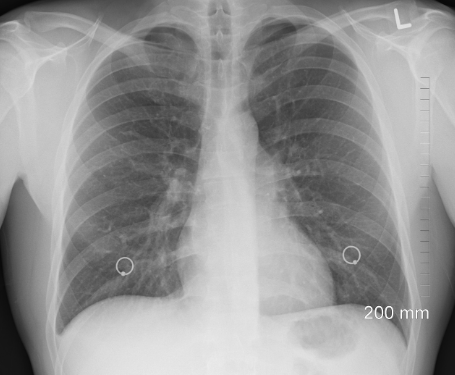

오늘은 흉골통증의 원인과 치료법에 대하여 알아보겠습니다. 흉골통은 가슴뼈에 불편함이나 고통이 느껴지는 것입니다. 흉골 통증의 원인은 다양하며 증상과 치료법도 다양합니다. 흉골 통증은 일시적이거나 만성적일 수 있으며 경미한 불편함부터 심한 통증까지 심각도가 다양합니다. 그러니까 흉골 통증의 근거를 찾아 적절한 치료법을 찾는 것이 필요합니다.